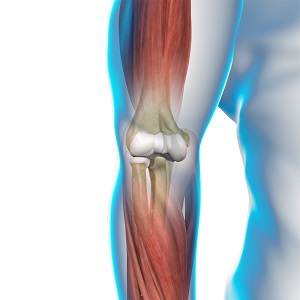

Triceps Injuries

The triceps or triceps brachii is a crucial muscle of the upper arm (humerus). It runs along the upper arm bone between the shoulder and elbow.